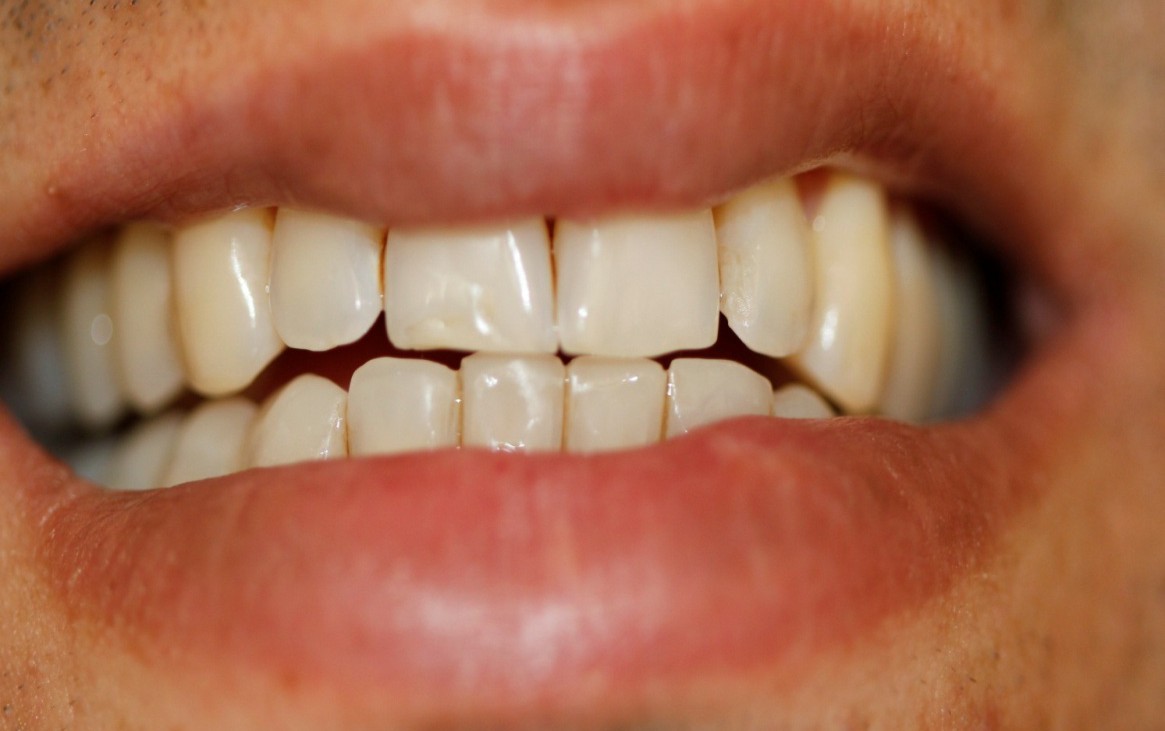

3- Maxila e mandibula atresiadas. (Overjet anterior de 5mm).

22- Reabilitação oclusal finalizada (cor A2) – dentes inferiores.

Placa de acetato de 1,5 mm para corrigir posição dos dentes 21 e 22.

23- Vista oclusal do alinhamento e nivelamento das overlays unitárias cimentadas.

Terços incisal e médio cor A2. Terço cervical A3.